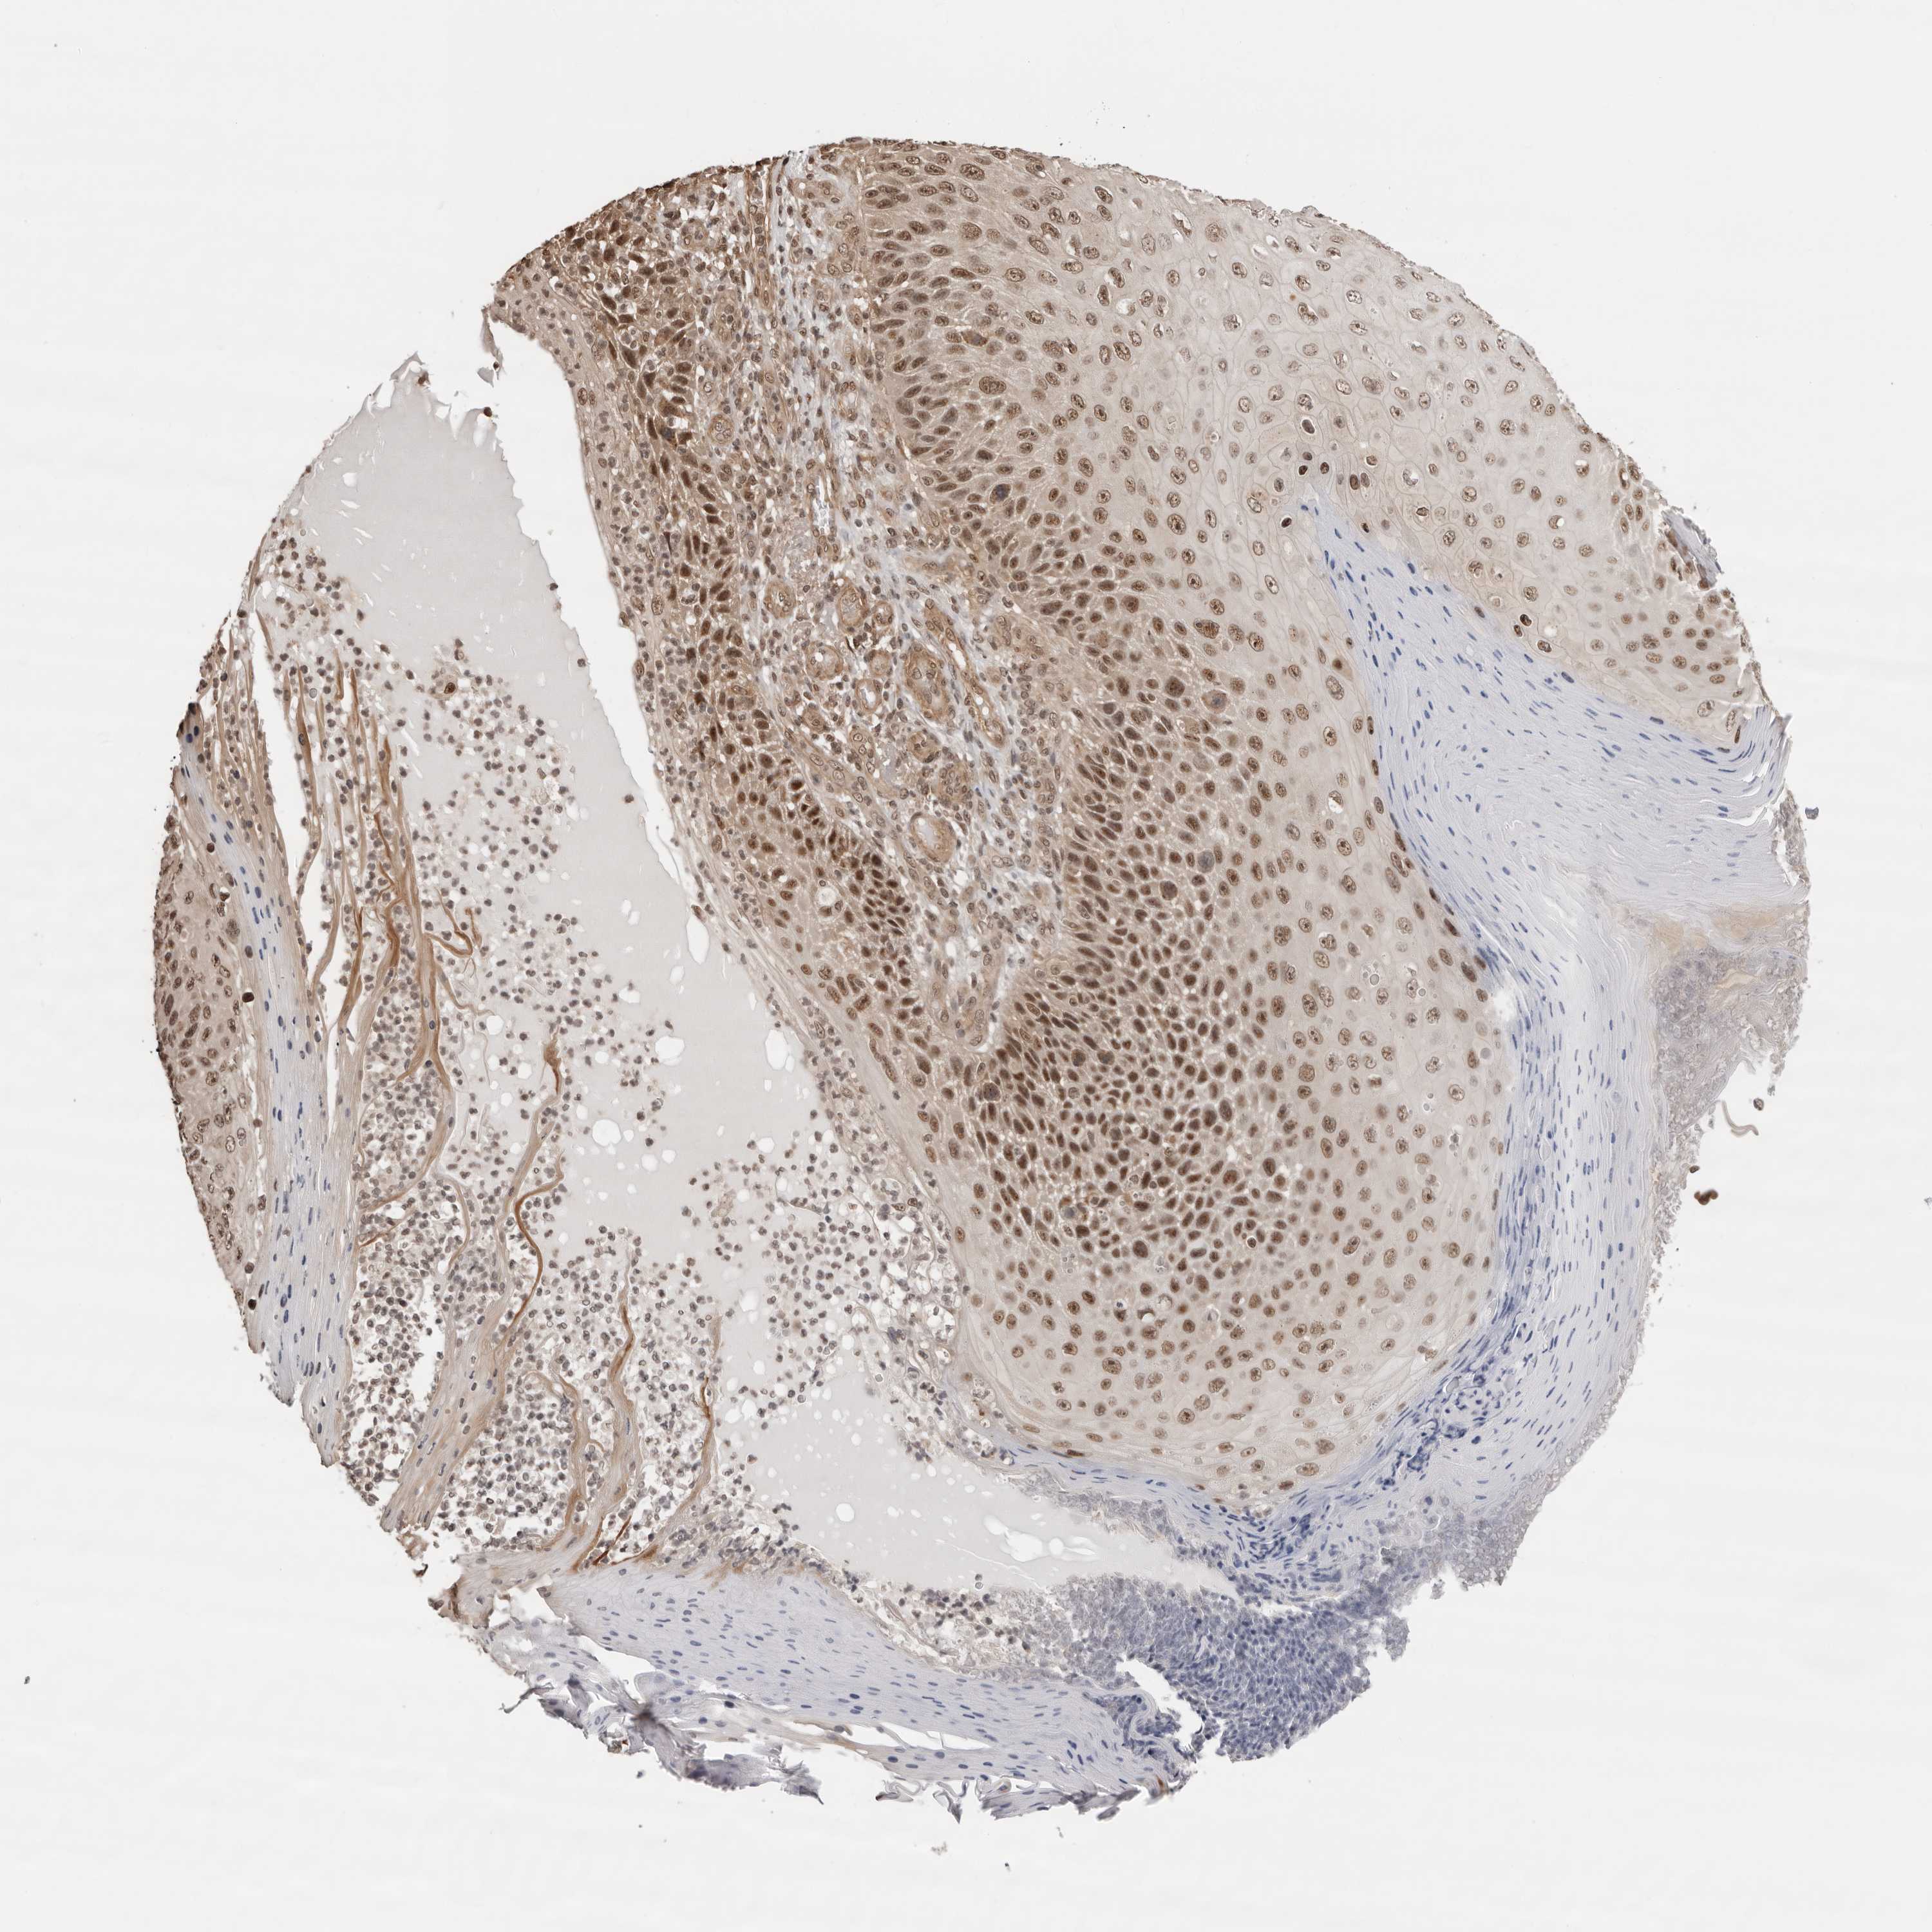

Basal cell and squamous cell cancer

SKIN CANCER - Protein expressioni

A mouse-over function shows sample information and annotation data. Click on an image to view it in a full screen mode. Samples can be filtered based on level of antibody staining by selecting one or several of the following categories: high, medium, low and not detected. The assay and annotation is described here.

Antibody stainingi

Antibody staining in the annotated cell types in the current human tissue is reported as not detected, low, medium, or high, based on conventional immunohistochemistry profiling in selected tissues. This score is based on the combination of the staining intensity and fraction of stained cells.

Each image is clickable and will lead to virtual microscopy that enables deeper exploration of all samples and also displays staining intensity scores, fraction scores and subcellular localization as well as patient and tissue information for each sample.

Antibody HPA028467

Staining

High

Medium

Low

Not detected

Intensity

Strong

Moderate

Weak

Negative

Quantity

>75%

75%-25%

<25%

None

Location

Nuclear

Cytoplasmic/membranous

Cytoplasmic/membranous,nuclear

Squamous cell carcinoma, metastatic, NOS

Squamous cell carcinoma, NOS